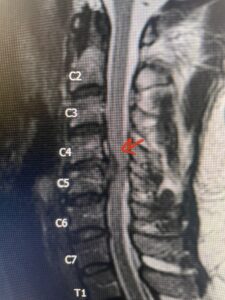

This 36-year-old female who had a long history of neck pain had a history on MRI of a C5-6 bulge. She recently after diving into a pool (not hitting her head on bottom) developed progressive problems with her arms. She had developed spontaneous shocks going down her arms and in the back of her neck. Spontaneous shocks going down the neck and spine is called a Lhermitte’s phenomenon and can occur with spinal cord compression and also with multiple sclerosis. On examination, the patient had long tract weakness of her arms, right greater than left. Her finger extensor weakness was profound on the right. MRI (Fig. 4) of the cervical spine revealed a massive C5-6-disc herniation causing significant cord compression right greater than left with subtle cord signal change. Because of the severe myelopathy, the patient was indicated for surgery. A C5-6 anterior cervical discectomy and fusion was performed (Fig. 5). The patient had a dramatic improvement of her strength in the recovery room.

Fig 4. Axial T2-weighted MRIs demonstrating large C5-6 herniated disc with spinal cord compression (red arrow)

Fig 4A. Axial T2 weighted MRIs demonstrating large C5-6 herniated disc with spinal cord compression (red-arrow)